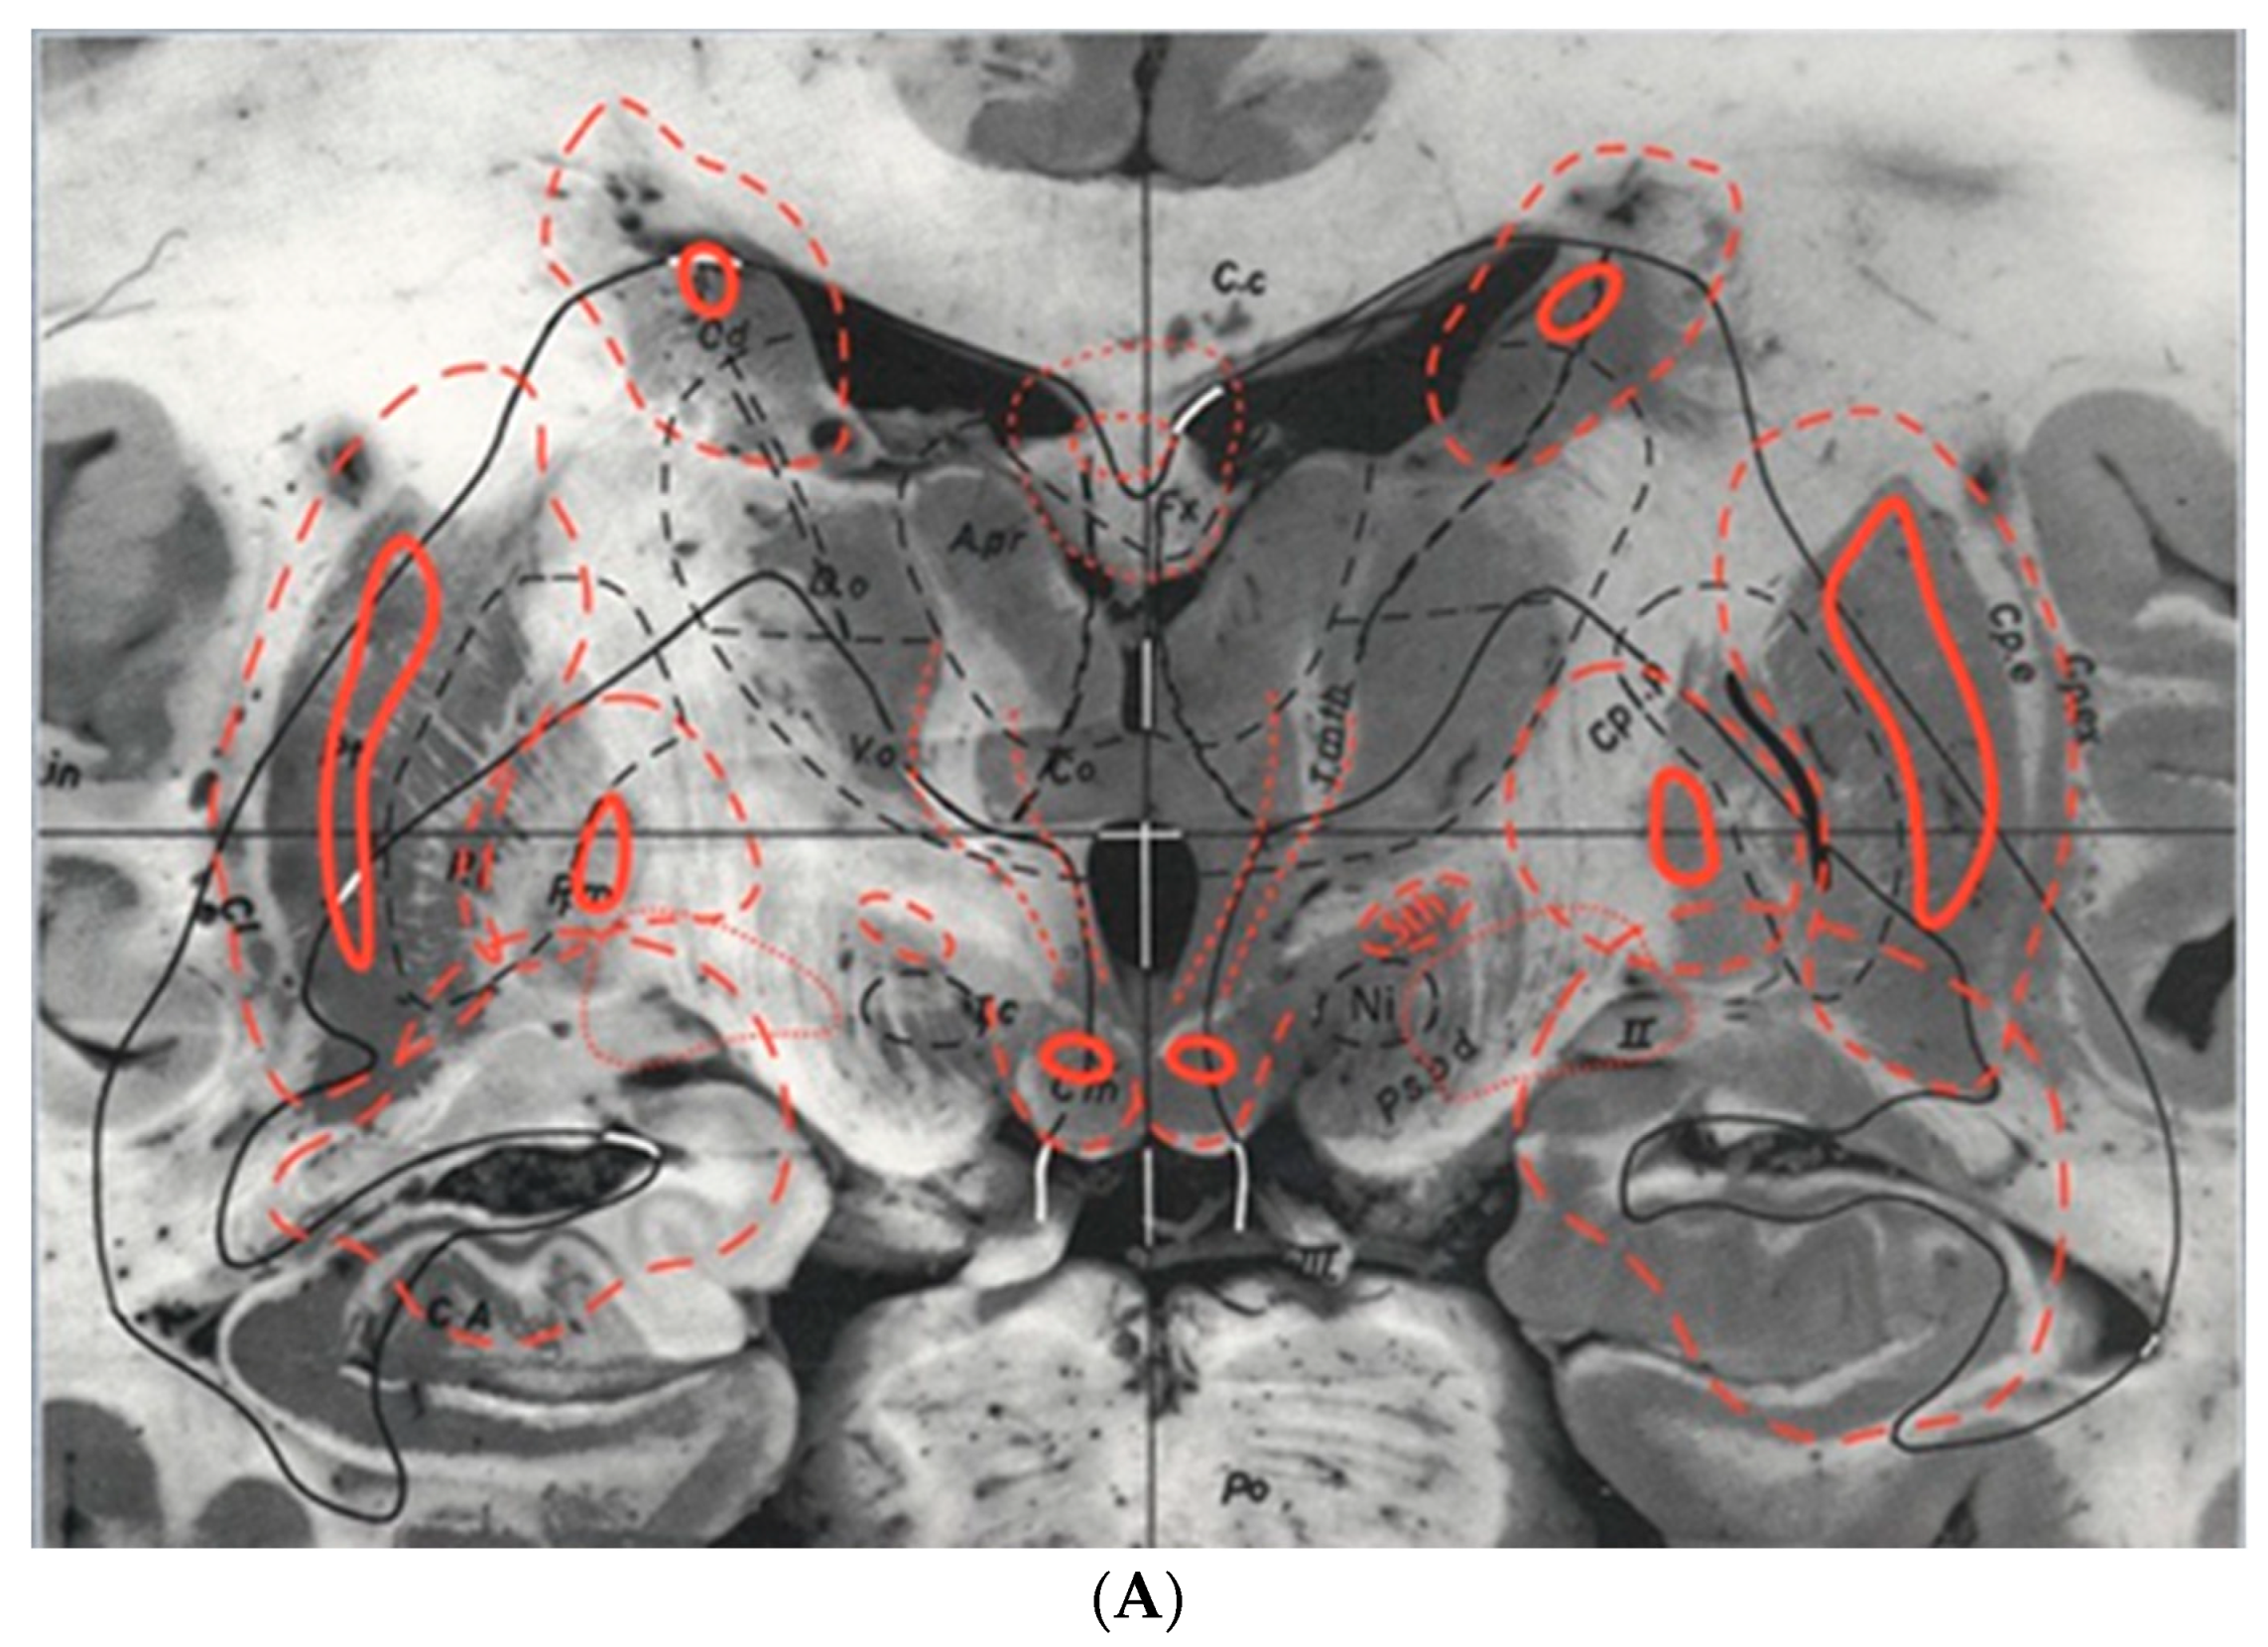

The Schaltenbrand–Wahren brain atlas was published in 1977 [21]. It differs from the Schaltenbrand and Bailey atlas, being based on myelin-stained sections instead of histological sections. The atlas contains 100 instead of 97 sections and it is overall organized in a different manner, with different levels of detail and different areas covered. The Schaltenbrand–Wahren atlas includes 34 macro-series photographs, all at 2× magnification and divided into three series as follows: 19 frontal planes from 57 mm anterior to 44 mm posterior to AC (Figure 4A), five sagittal planes from the midline (0 plane) to 22 mm lateral to the midline, six horizontal planes from 18 mm above to 20 mm below the IC line from one brain, and four additional horizontal planes from 5 mm to 28 mm below the intercommissural line from another brain. The authors recognized the importance that axial imaging would play in the future and gave relevance to the horizontal unstained macro-series and the myelin-stained micro-series. All horizontal sections are parallel to the intercommissural plane. The myelin-stained brainstem series comprises 21 planes in the transverse direction, as discussed earlier, and is not the only representation available. In fact, the atlas also includes the three conventional planes, resulting in a total of 78 myelin-stained atlas photographs. The 20 frontal planes extend from 16.5 mm anterior to 16.5 mm posterior to the midcommissural plane, 17 sagittal planes span from 1.5 to 27.5 mm lateral to the midline, and 20 horizontal planes cover a distance of 16 mm above to 9.5 mm below the IC line (as shown in Figure 4B).

Figure 4.

(A). Plate five from the Schaltenbrand–Wahren brain atlas showing the basal nuclei (from the Schaltenbrand and Wahren atlas, reproduced with permission; copyright Thieme: Stuttgart, Germany, 1977)) [21]. (B). Plate 43, brain LXXVIII, myelin-stained sagittal Section 12.0 mm from the midline. It is likely that this particular atlas section has been used to guide most stereotactic operations for movement disorders involving the subthalamic nucleus region in the modern era of MR-image-guided deep brain stimulation for Parkinson’s disease.. (from the Schaltenbrand–Wahren brain atlas, reproduced with permission; copyright Thieme: Stuttgart, Germany, 1977) [21].